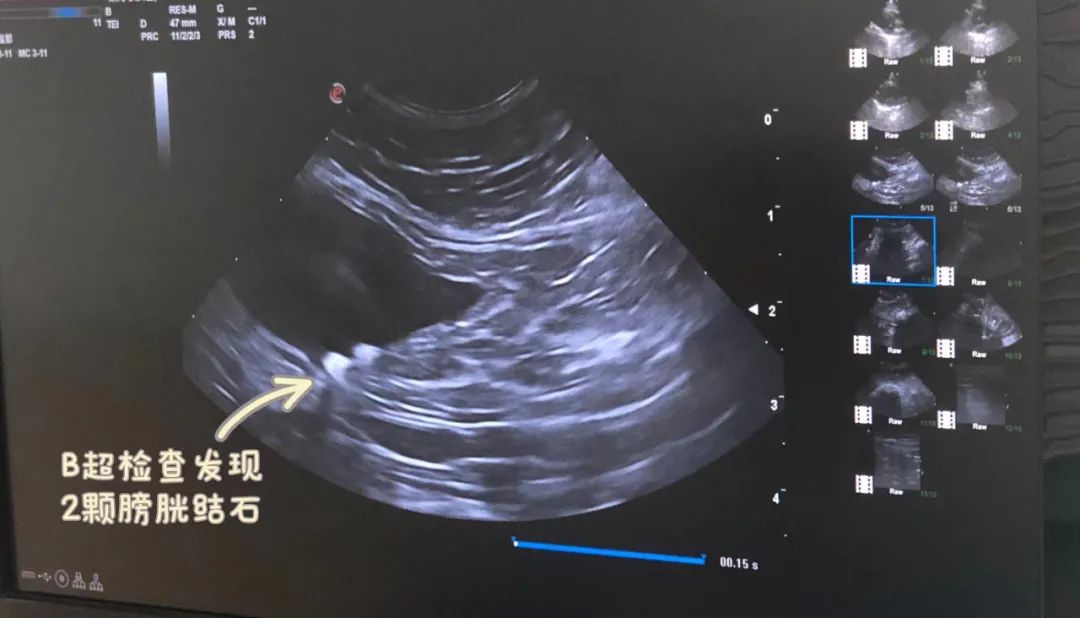

去年9月,带肥咪心月去宠福鑫回龙观分院做绝育。很多铲屎官听说过:布偶猫基因的原因,肾脏和心脏容易有问题。所以术前检查时医生建议增加了B超检查,肾脏和心脏没有异常,却发现了2颗 膀胱结石!

B超检查时发现了膀胱结石

当时结石5mm左右个头不大,还没有症状,再综合其他检查,医生判断属于较早期,疑似是 鸟粪石 (晶体),暂时不需要其他治疗,仅需要 更换泌尿道处方粮,多喝水,并定期体检 。